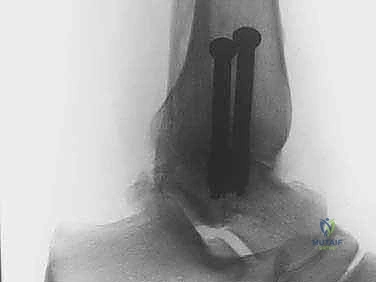

A 72-year-old male presents with chronic, intractable right shoulder pain and inability to actively elevate his arm above 60 degrees. X-rays

show severe glenohumeral osteoarthritis with significant superior migration of the humeral head and erosion of the acromion, consistent with rotator cuff arthropathy (Hamada Type IV). He has no prior shoulder surgery. Which of the following arthroplasty options is most likely to restore functional range of motion and pain relief?

Option D (Reverse total shoulder arthroplasty - rTSA) is the most appropriate treatment for this patient. The rTSA design medializes the center of rotation and increases the deltoid lever arm, allowing the deltoid to effectively elevate and abduct the arm, thereby compensating for the irreparable rotator cuff deficiency and addressing the pseudoparalysis. It reliably provides pain relief and functional improvement in this specific scenario, even with mild glenohumeral arthritis. The image provided shows superior migration and possible acromial erosion, which are common findings in rotator cuff arthropathy, reinforcing the choice of rTSA.